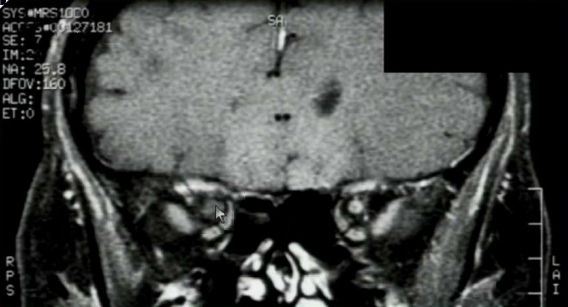

What is your diagnosis?

CN II is a part of the brain, so it is an optic nerve glioma.